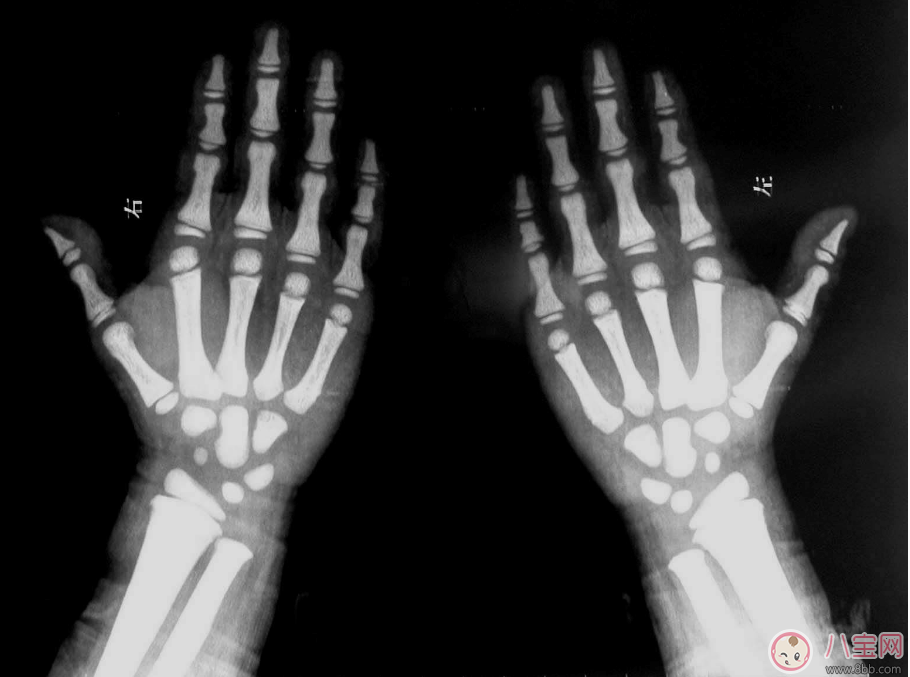

普通X線片即可確診。X線片上表現為:

①骨密度增高硬化廣泛均勻,骨小梁變粗、模糊,皮質增厚,髓腔狹窄,甚至消失;

②骨中骨:主要見于肋骨、肩胛骨及短管狀骨等;

石骨癥是一種少見的遺傳性疾病,臨床并不多見,容易出現漏診,診斷主要依靠X線的表現,有時需要通過生化和免疫學檢查結合CT、X線片才能確定其分型。同時要和某些化學元素中毒如:磷、鉛、氟中毒及成骨性骨轉移相鑒別。